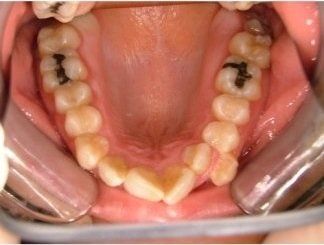

Il trattamento ortodontico non è solo per i bambini: se hai denti storti, affollati, mancanti o prominenti che ti impediscono di masticare e parlare liberamente, potrebbe essere necessario rivolgersi a uno specialista. L’ortodonzia prevede l'uso di apparecchi ortodontici, che possono essere fissi o rimovibili.

I dentisti studiano infatti le anomalie di costituzione, posizione e sviluppo di denti e ossa mascellari, e progettano l’apparecchio mirando al ripristino della corretta funzionalità dell'apparato masticatorio.